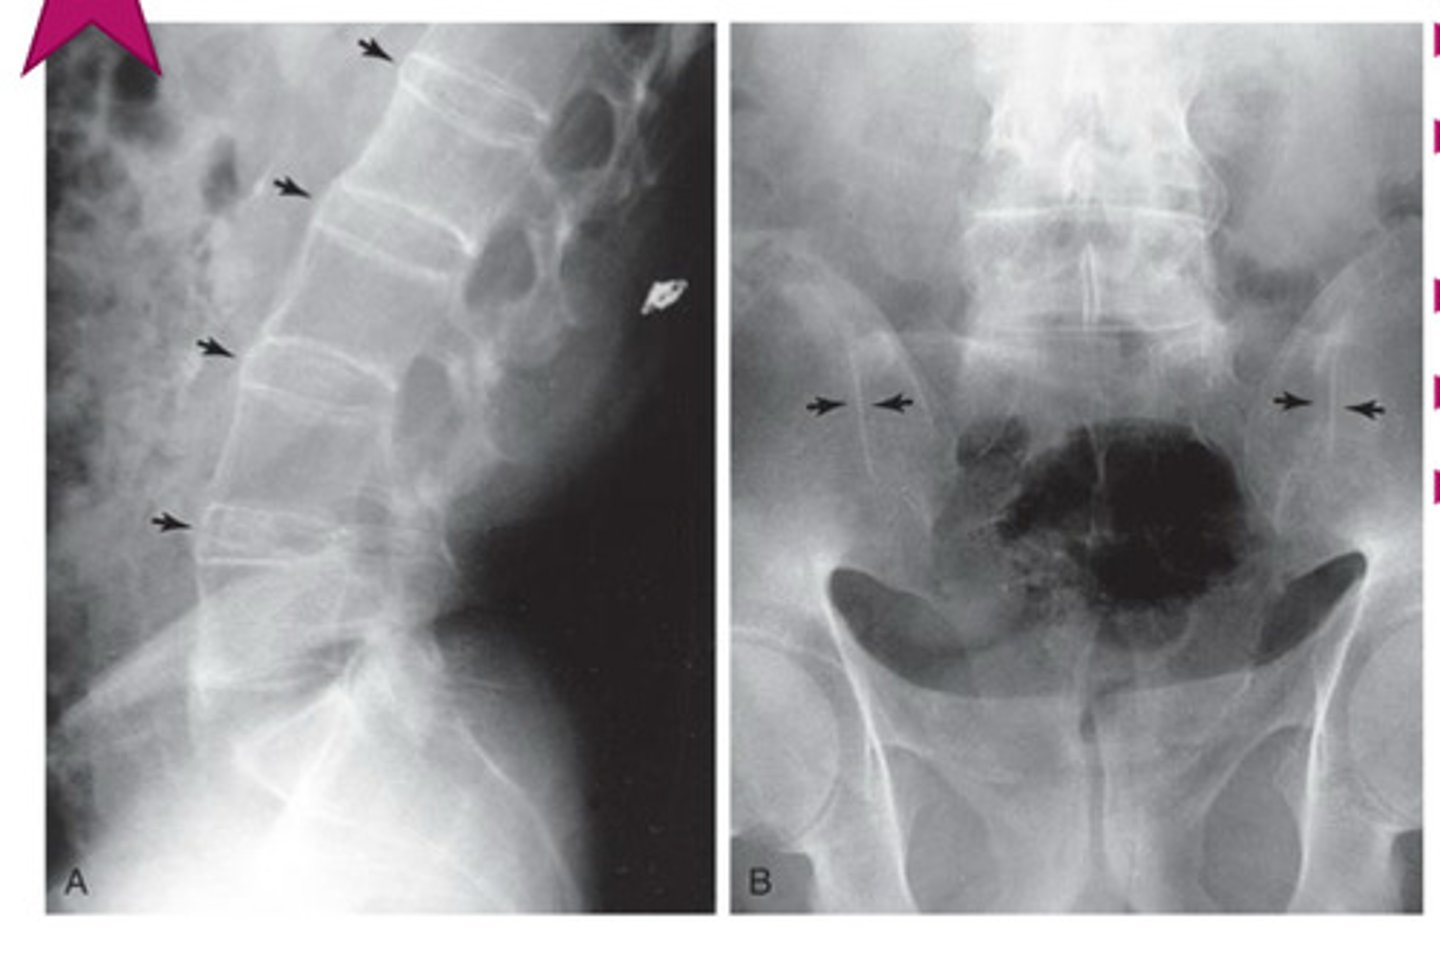

ankylosing spondylitis

young, males

neck/LBP, worse @ night & better w/ exercise

what is ankylosing spondylitis associated w/?

ulcerative colitis

what marker can do patients w/ ankylosing spondylitis test + for?

HLA-B27

hallmark of ankylosing spondylitis

fusion of lumbar spine & sacroiliac joints (sacroilitis)

bamboo spine ("dagger sign" on AP projection)

ankylosing spondylitis; no spaces b/w vertebrae